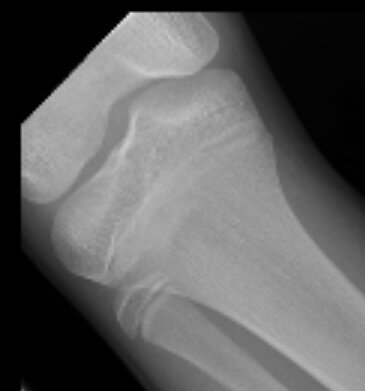

In a month I’ll start to drop updates but I want your thoughts. I also took photos of my growth plates.